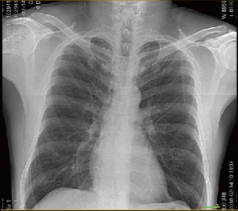

Chest X-Ray